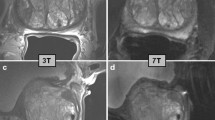

Common clinical MR systems employed for MR spectroscopy examinations have a field strength of 1.5T and 3T. Prostate MRSI at 3T can be performed at a higher SNR than at 1.5T, as illustrated by the two-fold increase in SNR for the inner citrate resonances, which enables MRSI with a higher spatial resolution [91]. Moving to 7T further increases SNR of prostate MRI 1.7- to 2.8-fold [92]. However, at this field it is more problematic to achieve sufficient RF power and field homogeneity in the prostate. These field-specific challenges are described in a separate paper in this issue [93]. At higher spatial resolution, the MRSI matrices to cover the whole prostate increase, which requires more repetitions in traditional 3D phase encode sampling and therefore may result in too long acquisition times for clinical exams, requiring accelerated acquisitions, e.g., with spiral readouts [94,95,96].

Endorectal or phased array RF coils

MRSI of the prostate commonly involves spin excitation with a body coil and signal reception with an external multi-channel phased array and/or an endorectal coil (Fig. 2) to receive the MR signal [17, 35, 97]. At 1.5T the use of an endorectal coil (ERC) is recommended if spatial resolutions below 1 cm3 are desired with sufficient spectroscopic SNR [20, 98, 99]. Endorectal coils are available in several versions requiring different operating procedures, each with specific benefits and disadvantages for MRS exams [100,101,102,103,104,105]. Although SNR is lower with phased array coils at 1.5T their use still may have diagnostic value [104].

At 3T MRSI can be performed without an ERC [106], but its use still improves cancer localization compared to using only external phased-array coils [107]. However, a comparison of PCa diagnosis by MRI at 1.5T with ERC and 3T without indicated a similar performance in cancer detection [108]. Although an ERC provides high SNR, especially near the coil, which can be exploited to reduce measurement time or to increase spatial resolution [83, 109] it has several disadvantages in clinical routine compared to phased array coils. For instance, an ERC is costly, its positioning is time consuming, requires experience, is uncomfortable for patients, is associated with signal drop in the coil FOV and causes artefacts [15]. Moreover, using an ERC reduces the SAR limit set by the MR system, which leads to longer acquisition times. Therefore, mpMRI of the prostate is now mostly applied at 3T without ERC, i.e., with external body phased array coils and hence it is relevant to demonstrate that clinical 3D MRSI of the prostate can also be performed without ERC at 3T [81, 88]. Using PRESS for acquisition, the quality of MRSI at 1.5 T with ERC is comparable to that at 3T without ERC, except for voxels located close to this coil, which have a higher SNR [110]. The loss in SNR by performing MRSI at 3T with a phased array coil combination instead of an ERC can be mitigated using LASER type of acquisition sequences [17, 28, 96]. Several studies have demonstrated that in this way MRSI of the prostate can be performed reliably within acceptable time in clinical routine [28, 82, 106, 111].